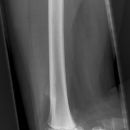

Femurschaftfraktur